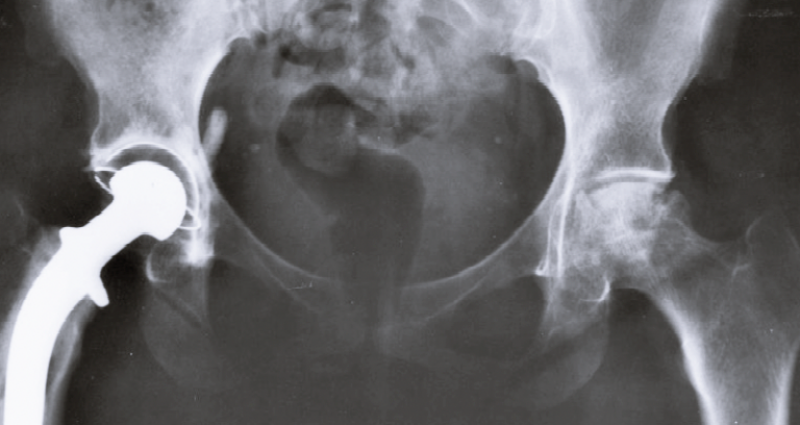

4. 고관절 골절

고관절 골절은 어떠한 외상으로 인해 대퇴골의 경부 또는 전자간부가 부러진 경우인데요. 상대적으로 뼈가 약한 노년층에서 그 발생빈도가 높습니다. 마찬가지로 고관절 골절이 일어나면 극심한 통증과 함께 움직임에 제한이 생기게 되므로, 나이가 있는 사람들의 경우 빠른 수술을 진행해야 합니다.